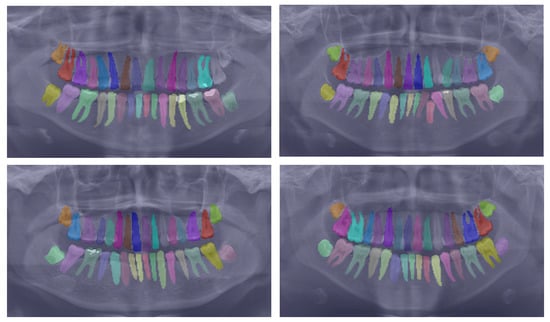

To further substantiate our comparison, we visualized the results from our proposed model. Figure 3 displays the instance segmentation results of various networks compared to the ground truth. Our method demonstrates closer alignment with the ground truth, indicating better performance in teeth instance segmentation tasks compared to the other methods. Notably, our proposed network maintains a consistent performance across all teeth, unlike the other networks. The synergistic benefits of the two tasks, SS and affinity pyramid, primarily drive the improvement in instance segmentation performance. Figure 4 depicts the results of panoptic segmentation with the background class (semantic segmentation) and tooth classes (instance segmentation). Figure 5 presents the precision–recall curve, which is the average of precision and recall for all classes. Panoptic segmentation improves the Dice score by also considering the surrounding tissues of teeth; thus, the loss also takes into account the background segmentation to yield better results.

Figure 4.

Showcasing the best panoptic segmentation results that encompass both the semantic segmentation of the background class and the instance segmentation of the teeth classes.